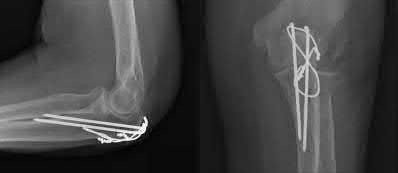

Question 1

A 5-year-old boy falls from monkey bars and sustains a widely displaced supracondylar humerus fracture. Upon presentation to the emergency department, the hand is pink but the radial pulse is absent. He undergoes prompt closed reduction and percutaneous pinning. Post-operatively in the recovery room, the radial pulse remains absent, but the hand is warm with brisk capillary refill (less than 2 seconds) and normal oxygen saturation on the index finger. Which of the following is the most appropriate next step in management?

Explanation

The patient has a 'pink, pulseless' hand following reduction and pinning of a supracondylar humerus fracture. Current pediatric orthopedic guidelines recommend observation for a well-perfused (pink, warm, brisk capillary refill) but pulseless hand post-reduction. The collateral circulation around the elbow is robust enough to maintain distal viability. Vascular exploration is indicated if the hand is white, cold, and poorly perfused (pulseless and ischemic) after a well-aligned reduction. Arteriography is generally not indicated and delays treatment if the limb is ischemic. Removing pins would destabilize the fracture and risk further neurovascular injury.